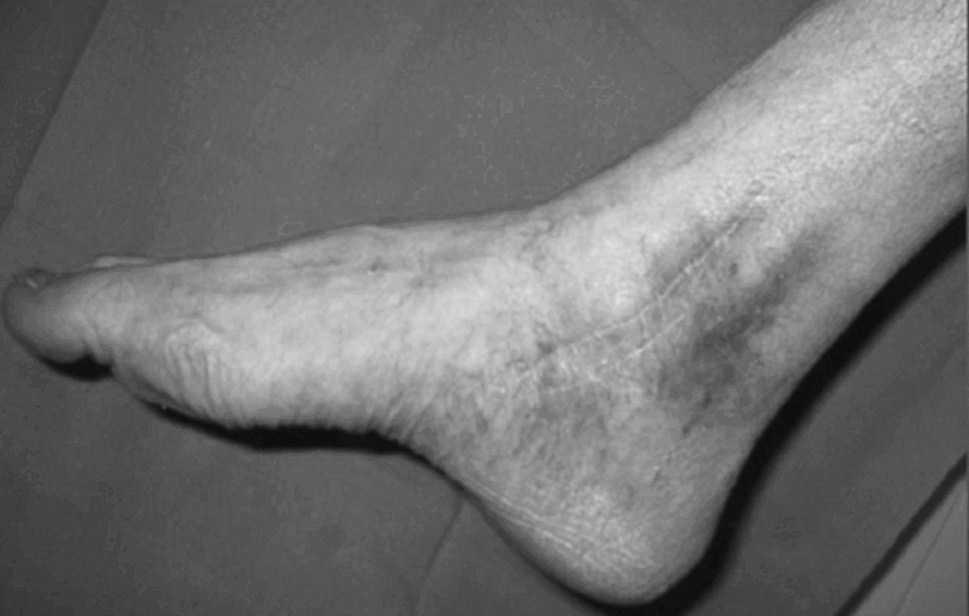

Respecto a las luxaciones del astrágalo, se han encontrado 7 casos de las cuales 5 (71,4%) de ellas eran luxaciones mediales --el pié se desplaza hacia adentro con respecto al astrágalo-- (figs. 13 y 14). La luxación medial es la más frecuentes --el 72% del total según DeLee y Curtis30 y Zimmer y Johnson31, y el 85% para Motley et al6--, seguidas de las laterales (de peor pronóstico) y mas infrecuentes las anteroposteriores.

Fig. 13. --Enucleación del astrágalo. Reducción, desbridamiento y estabilización temporal con agujas K.

Fig. 13. --Enucleation of the astragalus. Reduction, debridement and temporary stabilisation with Kirschner needles.

Fig. 14. --A) Radiografía al sexto mes: osteoporosis. B) Radiografía a los 18 meses: artrosis tibioastragalina.

Fig. 14. --a. Radiography at 6 months. b. Radiography at 18 months: tibio-astragalar arthrosis.